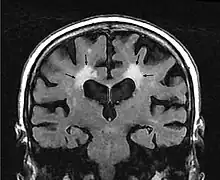

MRI image: Leukoaraiosis in a 90-year-old patient with cerebral atrophy.

Leukoaraiosis is a particular abnormal change in appearance of white matter near the lateral ventricles. It is often seen in aged individuals, but sometimes in young adults.[1][2] On MRI, leukoaraiosis changes appear as white matter hyperintensities (WMHs) in T2 FLAIR images.[3][4] On CT scans, leukoaraiosis appears as hypodense periventricular white-matter lesions.[5]

The term "leukoaraiosis" was coined in 1986[6][7] by Hachinski, Potter, and Merskey as a descriptive term for rarefaction ("araiosis") of the white matter, showing up as decreased density on CT and increased signal intensity on T2/FLAIR sequences (white matter hyperintensities) performed as part of MRI brain scans.

These white matter changes are also commonly referred to as periventricular white matter disease, or white matter hyperintensities (WMH), due to their bright white appearance on T2 MRI scans. Many patients can have leukoaraiosis without any associated clinical abnormality. However, underlying vascular mechanisms are suspected to be the cause of the imaging findings. Hypertension, smoking, diabetes,[3] hyperhomocysteinemia, and heart diseases are all risk factors for leukoaraiosis.